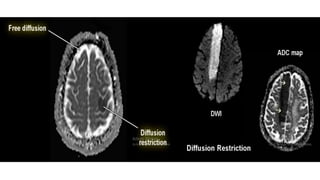

DIFFUSION TRACE

• Isotropic diffusion is the basis of DWI.

• However, there are some anisotropy

of water molecules in the tissues .

• To reduce this anisotropy ,the image

with higher b value like b=1000 is

acquired in three directions along X,Y,Z

axes.

• Diffusion changes along all 3 axes are

then averaged out to get a “TRACE “

diffusion image.